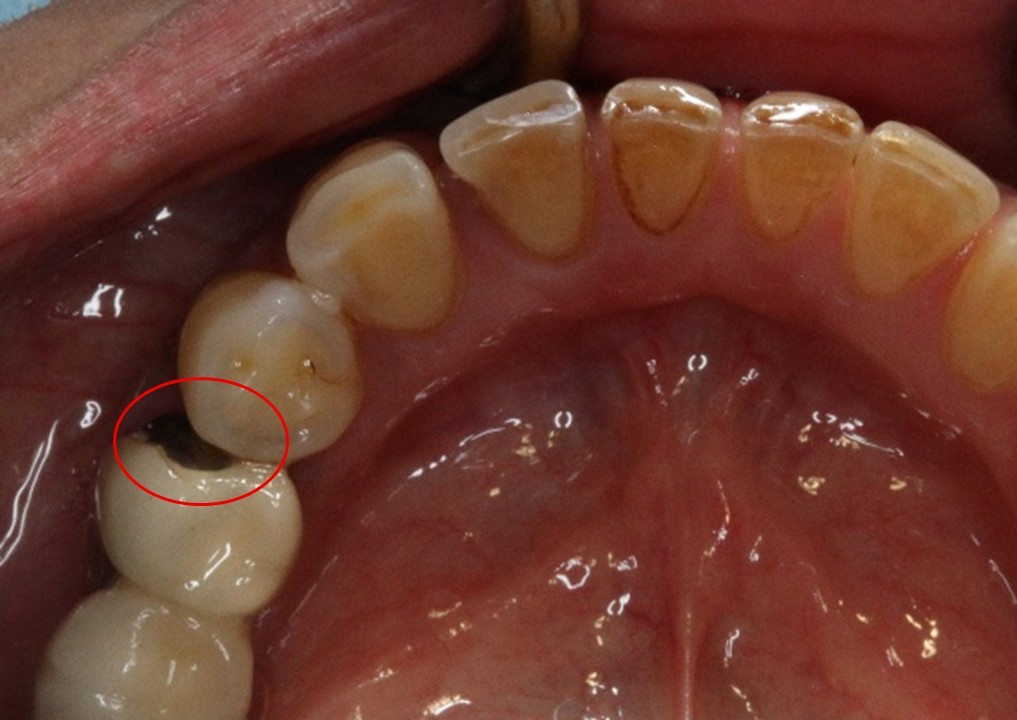

瓷崩-蒔雨牙醫診所

瓷崩